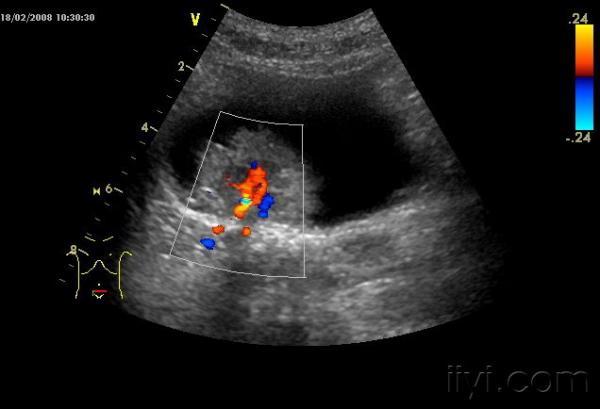

肿瘤内丰富血流